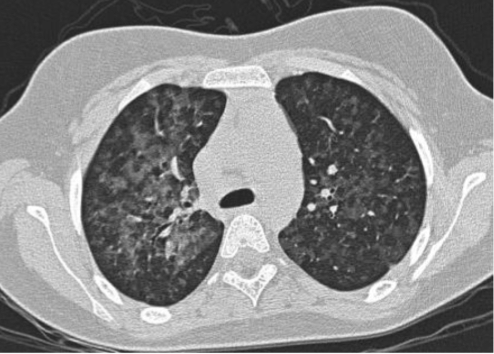

Is this UIP?

No, this is not UIP because this is upper-lobe predominant fibrosis